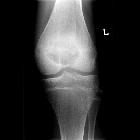

osseous lesions preferentially involving the epiphysis

Epiphyseal lesions comprise tumors and other pathologies that occur around the epiphysis and any epiphyseal equivalent bone.

Common differential diagnoses include the following :

- chondroblastoma: rare epiphyseal tumor found in young adults; it usually does not extend into the metaphysis, and usually does not extend beyond the bone

- giant cell tumor (GCT): occurs in adolescents in whom the epiphyseal growth plates have closed; it can extend to involve the adjacent metaphysis

- geode/intraosseous ganglion

- osteomyelitis

- clear cell chondrosarcoma

- others that occur rarely

- osteosarcoma and osteoblastoma

- aneurysmal bone cyst (ABC): usually metaphyseal, but if it occurs after the growth plate is obliterated, it may extend into the epiphysis

- brown tumor

- haemophilic pseudotumor

- enchondroma

- eosinophilic granuloma

- osteoid osteoma